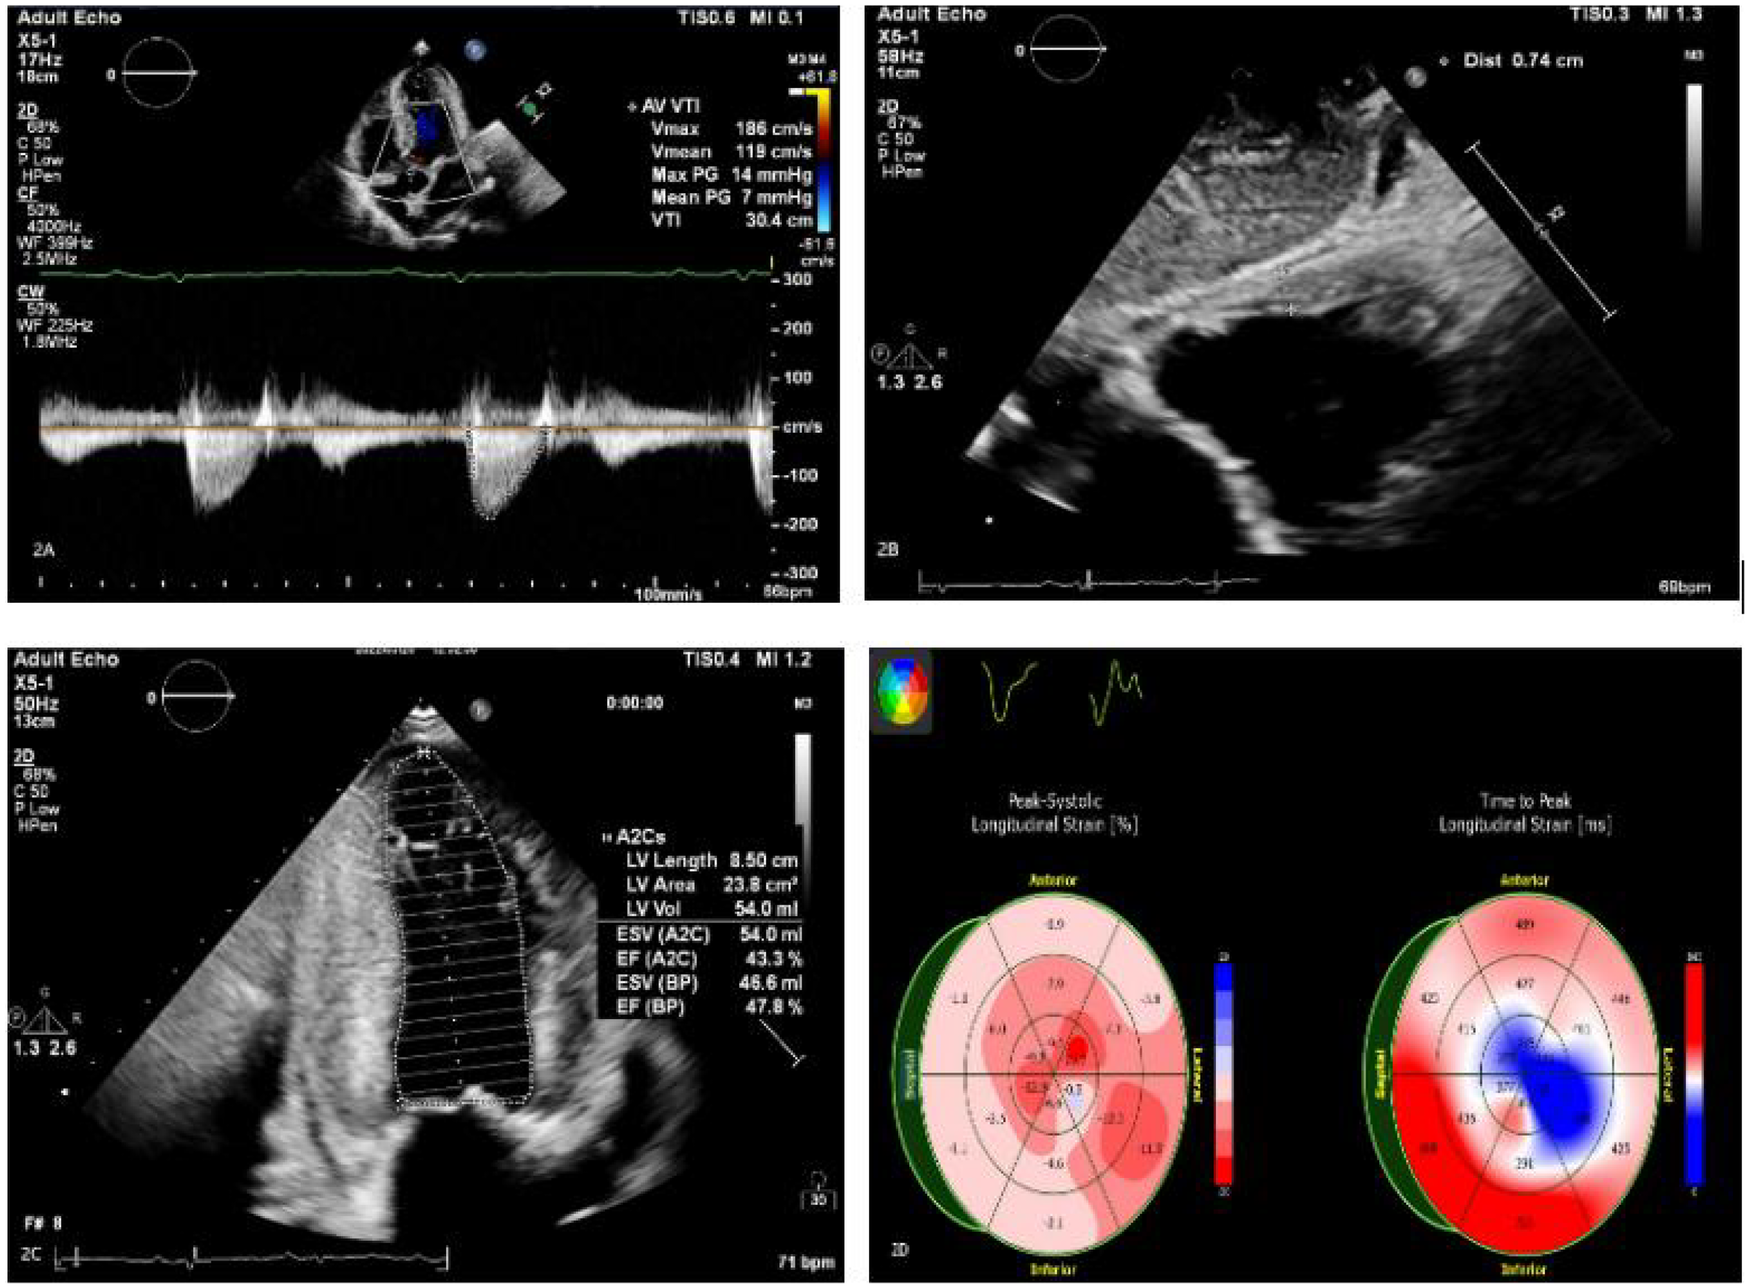

The patient is a 50-year-old male who was admitted to the hospital on March 28, 2022, due to “chest tightness and dyspnea for 3 weeks after physical activity.” Physical examination revealed BP: 100/60 mmHg, HR: 150 beats per min, with an absolutely irregular heart rhythm, and oxygen saturation of 100%. The cardiac dullness border was enlarged; no jugular venous distension was observed, and pitting edema was present in both lower limbs. Muscle strength in all four limbs was normal.An electrocardiogram (ECG) (Figure 1) showed rapid atrial fibrillation with low voltage in limb leads. Echocardiography (Figure 2) suggested a primary consideration of cardiac amyloidosis: enlarged left atrium, symmetrical thickening of the left ventricular myocardium, dense and enhanced myocardial echoes with granular sparkling strong echoes, thickened right ventricular wall (free wall thickness 0.74 cm), preserved apical strain in the left ventricle presenting a “cherry on top” sign (LV GLS = −6.2%), thickened mitral and tricuspid valves with mild regurgitation, reduced left ventricular systolic function (EF: 47.8%), decreased left ventricular diastolic function (grade 3), and a small amount of pericardial effusion. The aortic valve had a congenital bicuspid malformation (Type 1), with currently acceptable valve function. Chest CT revealed moderate pleural effusion bilaterally with adjacent lung tissue atelectasis (Figure 3). Blood tests showed NT-proBNP: 5,150 pg/mL (normal: <125 pg/mL below75 years old), BNP: 650.4 pg/mL (normal: <100 pg/mL), LDH: 253 U/L (normal: 125–220 U/L), CK: 73 U/L (normal:38–174 U/L), CK-MB: 20 U/L (normal: <5–25 U/L), cTnI: 0.048 ng/mL (normal: <0.04 ng/mL).

Figure 2

(A–C) Echocardiography findings include an enlarged left atrium and symmetrical thickening of the left ventricular myocardium (LVPWd 1.48 cm). Dense, granular sparkling echoes in the myocardium are observed, along with thickened right ventricular walls (free wall thickness 0.74 cm). Both mitral and tricuspid valves are thickened with mild regurgitation. There is reduced left ventricular systolic function (EF: 47.8%) and severely reduced left ventricular diastolic function (grade 3). A small amount of pericardial effusion is present. (D) The left ventricle shows preserved apical strain, presenting as a “cherry on top” sign. The left ventricular global longitudinal strain (LV GLS) is −6.2% (Left Ventricular Global Longitudinal Strain is a sensitive parameter for assessing left ventricular myocardial systolic function, derived from speckle-tracking echocardiography).